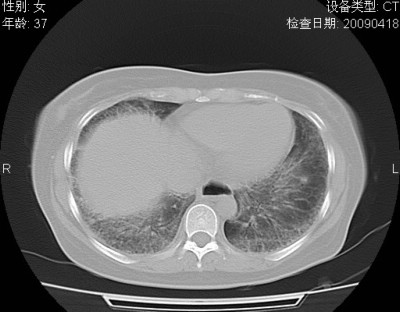

以下是引用随光逐影在2009-4-20 8:03:00的发言:[br]两肺间质性病变(间质性肺炎?特发性肺间质纤维化?)。

以下是引用51736011在2009-4-21 16:24:00的发言:[br]两肺间质性病变(间质性肺炎?特发性肺间质纤维化?)。